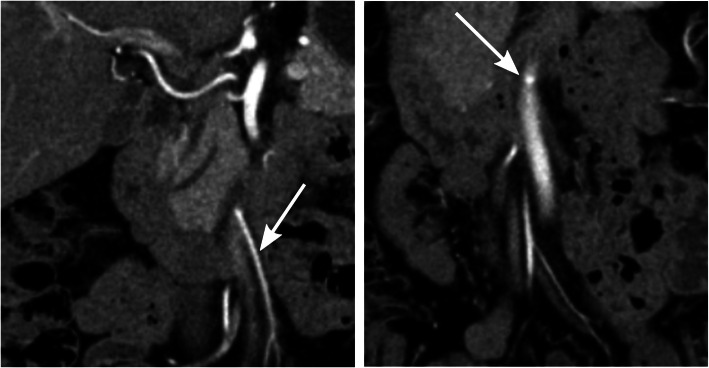

Typically, after low ligation, the IMA was moved laterally when compared to the preoperative examination, and the remaining left colic artery extended upward towards the remaining descending or sigmoid colon. After high ligation, there was usually a remaining small short stump of the IMA or a small bud-like bulge at the exit from the abdominal aorta (Fig. 3).

Fig. 3.

Example of where the ligation level was registered as low in the Swedish Colorectal Registry but where the radiological examination determined that the ligation level was high. In the preoperative image to the left, the inferior mesenteric artery (IMA) is indicated with an arrow. The postoperative image to the right demonstrates that all that remains of the IMA is a small bud-like contrast-filled bulge at the exit from the aorta